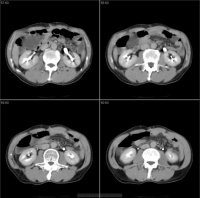

其真正的发病率尚不清楚,目前临床上的病理有增多的趋势,其原因与B超CT等影象学诊断方法普及有关。肝囊肿中以孤立性囊肿及多囊肝多见,孤立性肝囊肿通常无任何症状,若囊肿较大可出现压迫症状,如腹痛恶心腹泻等。囊肿的发生部位以右肝居多。多发性肝囊肿又称多囊肝,有半数以上的病人合并有多囊肾,多囊肝常侵犯整个肝脏,也有少数多囊肝病人的病变局限于肝脏的一叶或半肝范围。

多发性肝囊肿又称多囊肝,有半数以上的病人合并有多囊肾,多囊肝常侵犯整个肝脏,也有少数多囊肝病人的病变局限于肝脏的一叶或半肝范围。

多囊肾60岁以上的患者70%发现多囊肝,尸解材料更多见,90%以上病例有多囊肝,发生率并不与肾囊肿的严重程度相平行,一般较肾囊肿晚发现10年,且发展更慢。女性(特别是经产妇)发病率高且发病年龄提前,囊肿数目较多,可能是女性激素参与其形成。